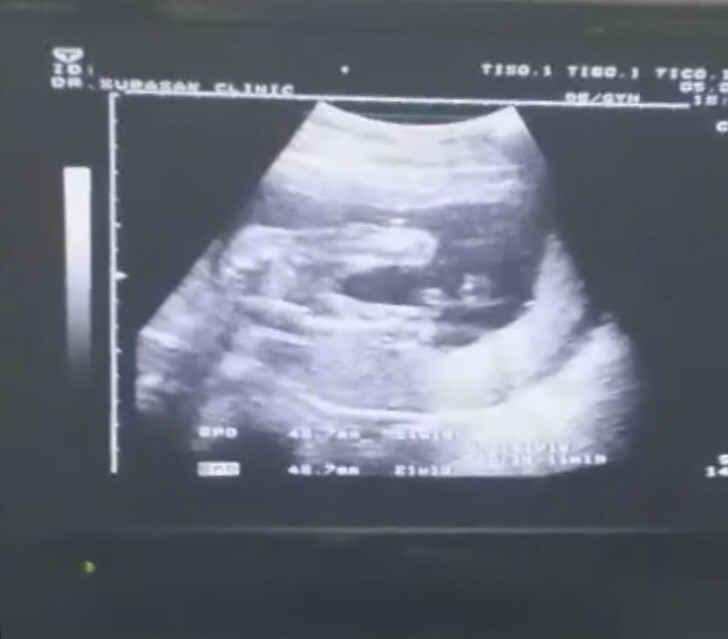

คุณแม่ท่านไหนคลอดเดือนพย.62มั้งค่ะขอเสียงหน่อย ได้ลูกสาวหรือลูกชายกันค่ะ ? บ้านนี้วันนี้พึ่งไปอัลตร้าซาวมาเป็นลูกสาวกำหนดคลอด21พย.ค่ะเห็นจิมิชัดมาก